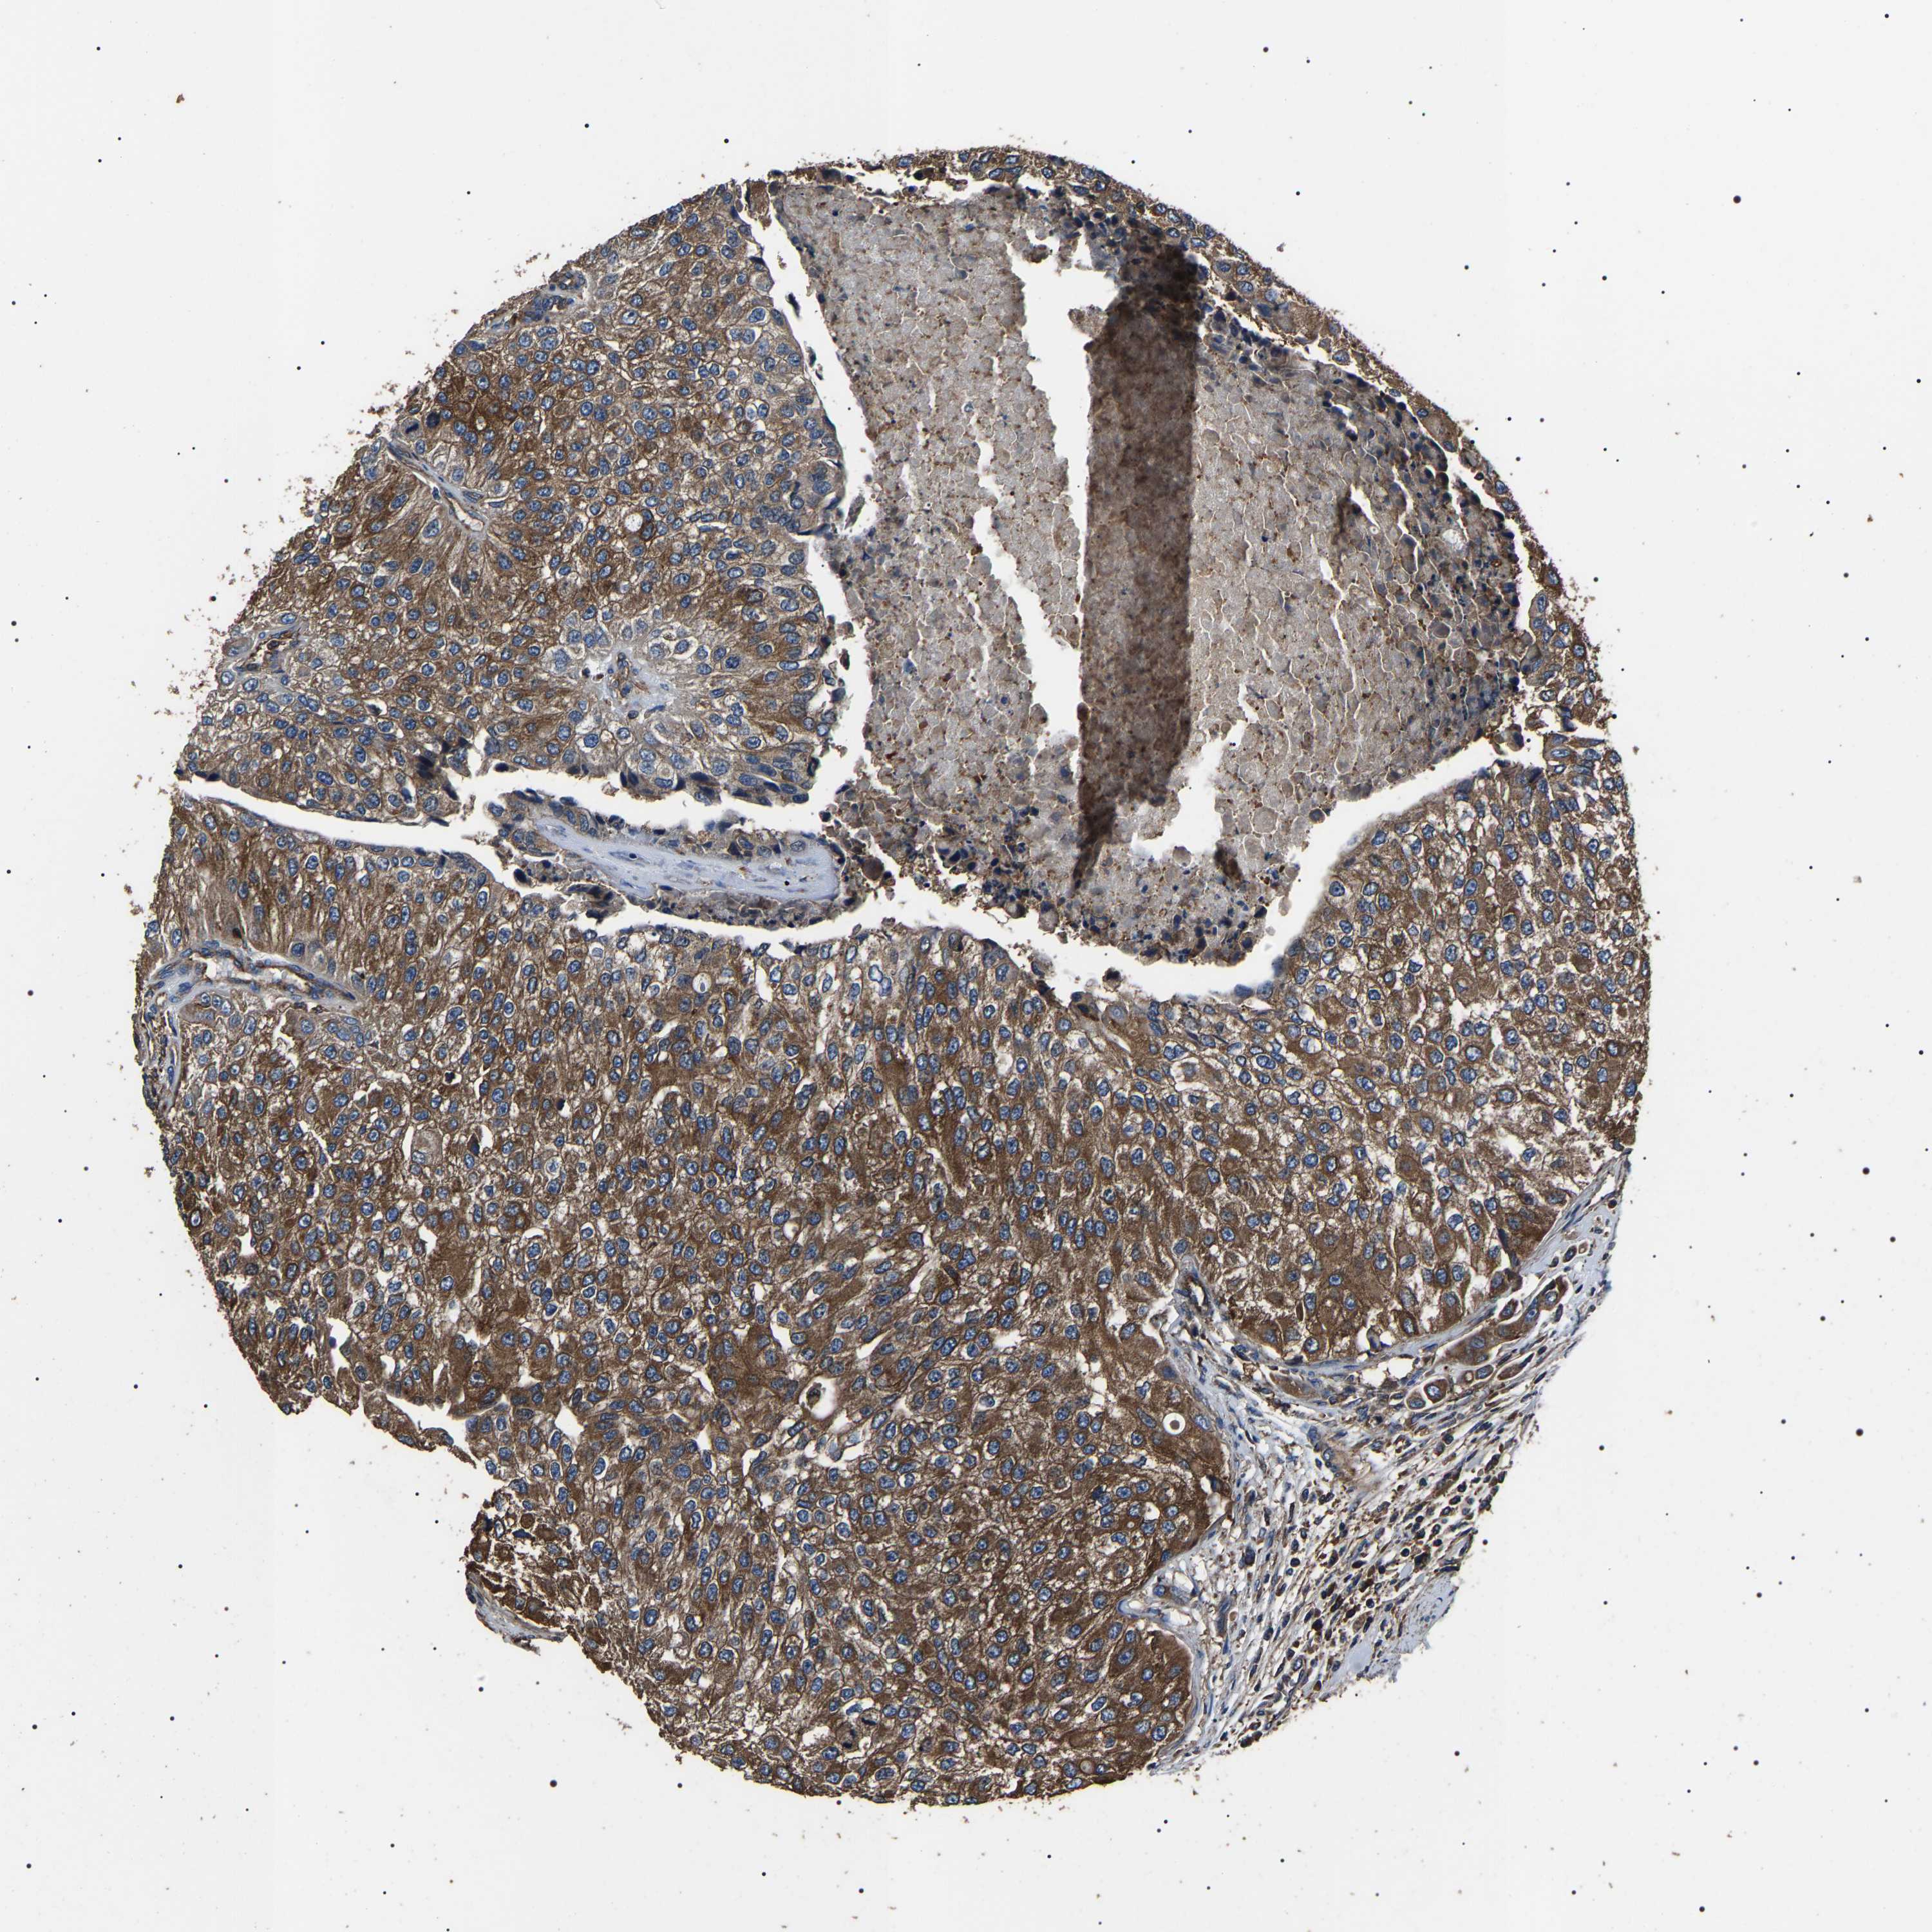

UROTHELIAL CANCER - Protein expressioni

A mouse-over function shows sample information and annotation data. Click on an image to view it in a full screen mode. Samples can be filtered based on level of antibody staining by selecting one or several of the following categories: high, medium, low and not detected. The assay and annotation is described here.

Antibody stainingi

Antibody staining in the annotated cell types in the current human tissue is reported as not detected, low, medium, or high, based on conventional immunohistochemistry profiling in selected tissues. This score is based on the combination of the staining intensity and fraction of stained cells.

Each image is clickable and will lead to virtual microscopy that enables deeper exploration of all samples and also displays staining intensity scores, fraction scores and subcellular localization as well as patient and tissue information for each sample.

Antibody HPA018447

Staining

High

Medium

Low

Not detected

Intensity

Strong

Moderate

Weak

Negative

Quantity

>75%

75%-25%

<25%

None

Location

Nuclear

Cytoplasmic/membranous

Cytoplasmic/membranous,nuclear

Urothelial carcinoma, Low grade

Urothelial carcinoma, High grade